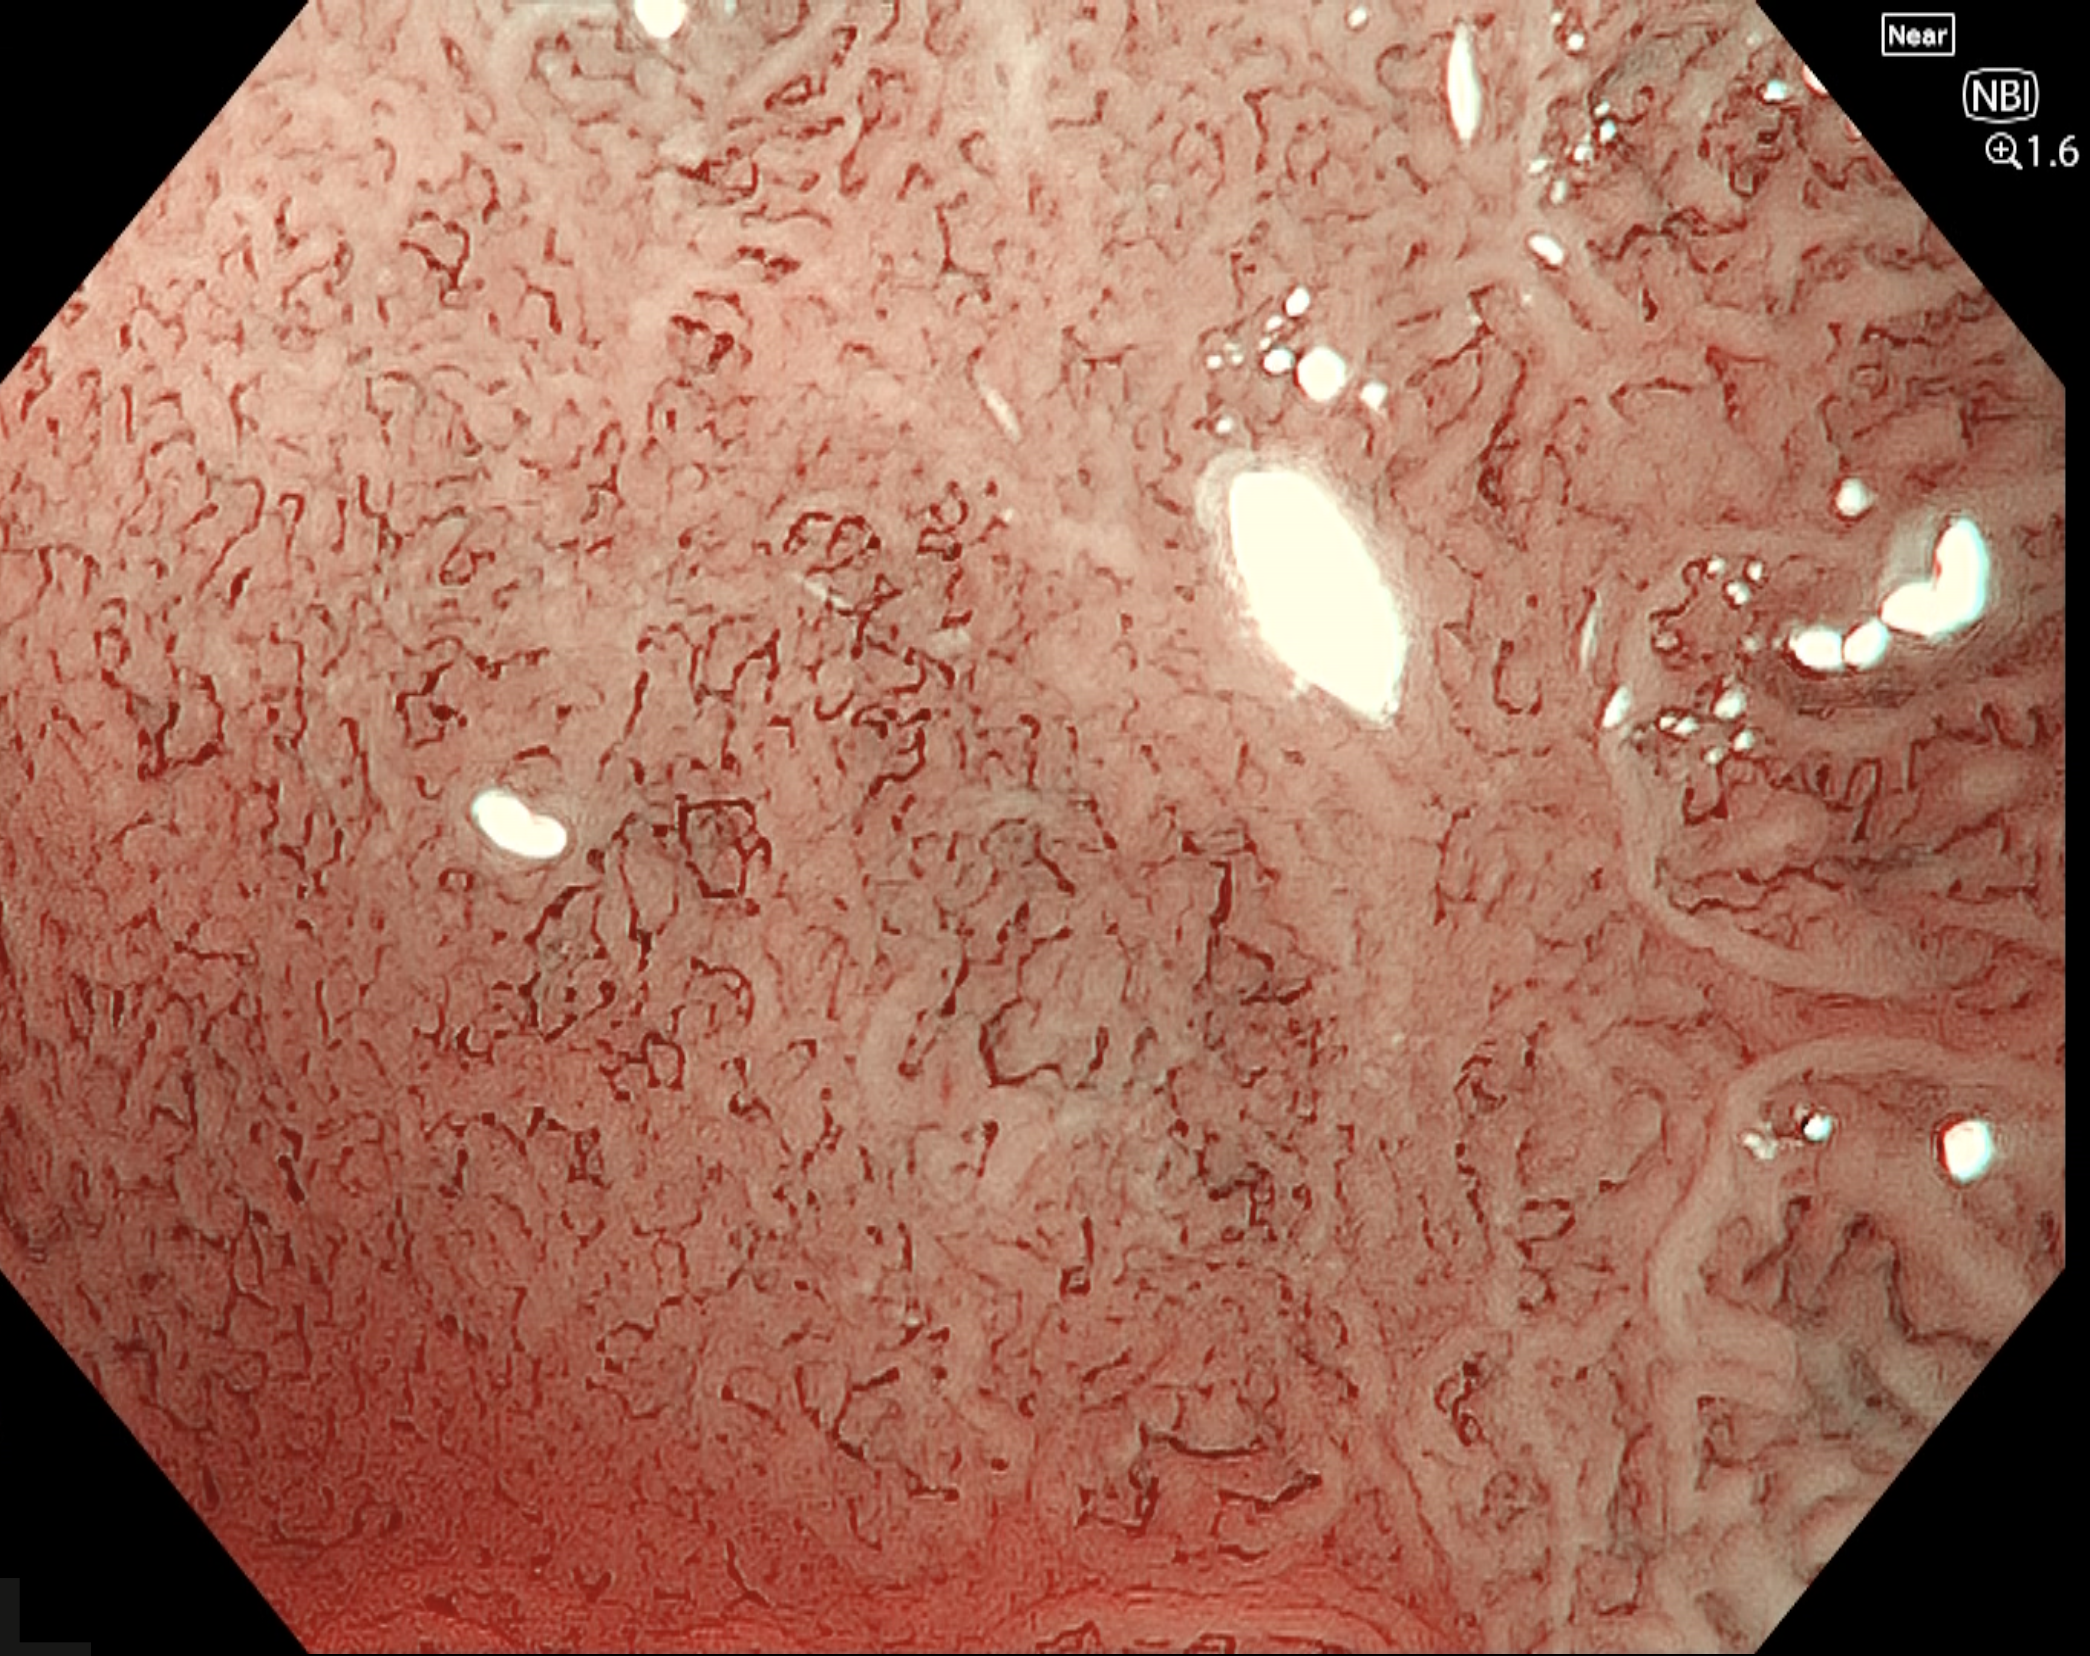

• NBI観察(電子拡大)

強調設定:B8

図6

near focusモードに電子拡大1.6倍を併用することで、腫瘍肛門側における表面微細構造および微小血管構築像の詳細観察が可能となっている。